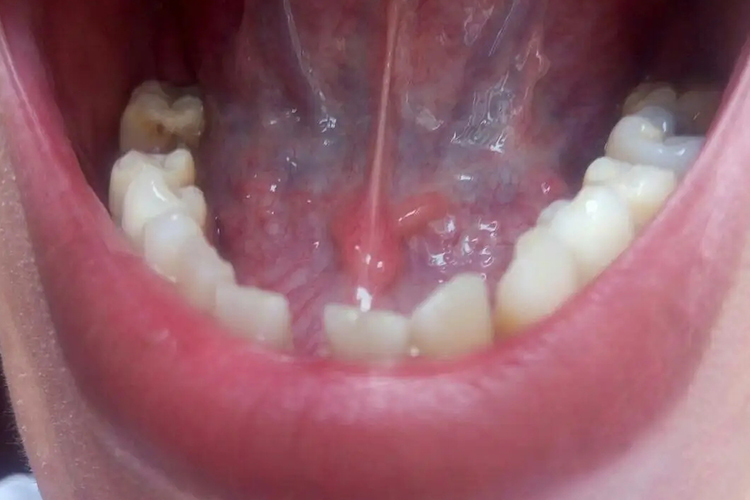

单纯疱疹表现为舌根处出现成簇小水疱,似针头大小。小水疱疱壁薄、透明,易溃破,形成不规则形糜烂面,如有继发感染,可形成溃疡。患者疼痛明显,影响进食与说话。

口腔黏膜的损害表现为疱疹密集成簇,疱疹破溃会形成较大的糜烂面,病损仅限于单侧,表面覆盖有黄白色假膜,黏膜充血,疼痛明显。

手足口病表现为舌根部有散在的红斑及小疱疹,多与皮疹同时出现,或稍晚1-2天出现。口内疱疹极易破溃成糜烂面,上覆灰黄色假膜,周围黏膜充血红肿。